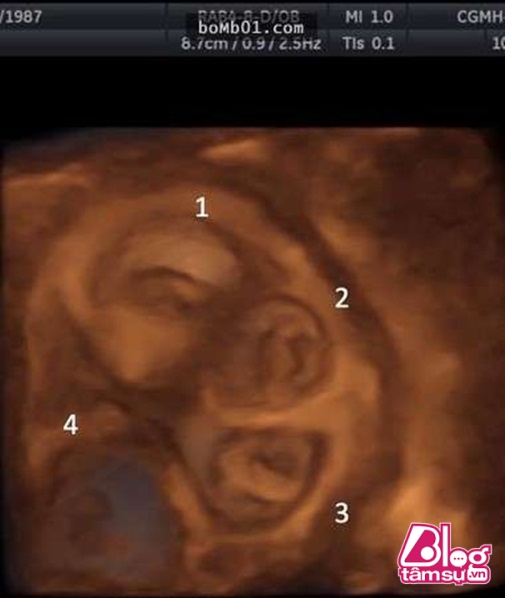

Tuy nhiên, sau 1 thời gian sử dụng thuốc, cô gái liên tục bị những cơn đau bụng hành hạ, cô đã đến gặp bác sĩ để kiểm tra ngã ngửa khi nhìn thấy những hình ảnh siêu âm. Theo các bác sĩ, trong cơ thể cô gái có tim thai đang đập và nó đang gây nguy hiểm đến tính mạng của cô gái.

Các bác sĩ cho rằng, cô gái trẻ đã mang thai ngoài tử cung và đây còn là song thai. Đây là 1 trường hợp rất hiếm, nó có thể gây nguy hiểm cho cả mẹ và 2 đứa trẻ nhưng cô gái và gia đình vẫn quyết định giữ lại song thai này.

Sau đó ít ngày, cô gái bỗng bị đau bụng 2 bé trai vô cùng đáng yêu đã chào đời. Trường hợp của cô gái là trường hợp rất hiếm trên thế giới vì theo như bình thường những người mang thai ngoài tử cung sẽ rất khó có thể giữ lại đứa trẻ và cô gái này còn mang song thai. Mặc dù không được chăm sóc như những thai nhi bình thường khác nhưng may mắn 2 bé trai vẫn được phát triển bình thường. Mong rằng 2 bé sẽ có tương lai tươi sáng.